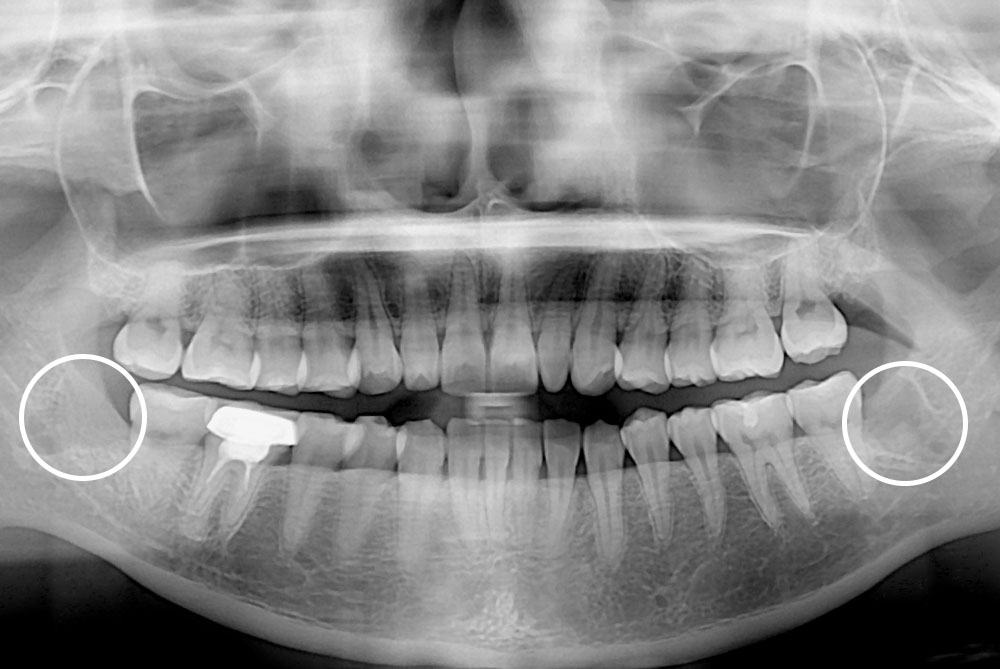

[사랑니] 매복 사랑니 발치

치료전 : 2018-03-07